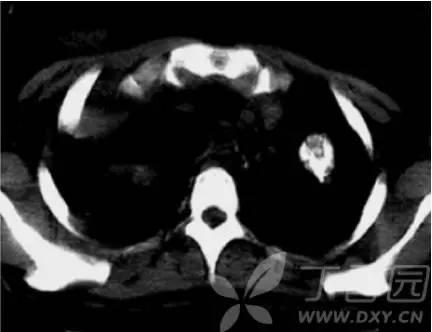

转移性肺癌 CT表现特点由丁香站友分享,大家一起来读片。 1弥漫性肺转移瘤的 CT表现 1.血行性转移:表现为两肺多发或弥漫性粟粒状、结节状病灶,大小不一,多为圆形或类圆

转移性肺癌是指来源于其它组织的肿瘤,通过血行转移的方式,转移至肺部。转移性肺癌的原发灶常为脑部肿瘤、骨肿瘤、胃肠道肿瘤。转移性肺癌,在CT影像学中表现为大小不